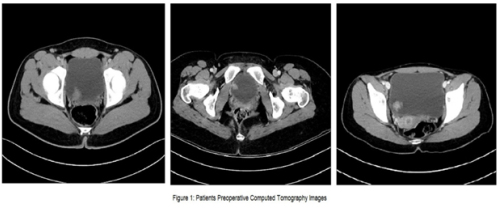

Vinay Nagendra Kaushik, Gopalkrishna Sp, Srikanth Kulkarni

Malakoplakia, derived from the Greek term for "soft

plaque", [] is a rare chronic inflammatory disease first

identified by Professor von Hansemann in 1901 and reported

by Michaelis and Guttman in 1902. Although benign, it

frequently resembles malignant carcinomas due to its tumorlike

mass formations, complicating its diagnosis. Depending

on the location, the disease typically manifests as raised, grey

lesions of varying sizes or soft, yellow mucosal plaques during

physical examination [].

Though malakoplakia can affect multiple organs, it

primarily targets the urinary system, especially the bladder,

with less frequent involvement of the kidneys and ureters [].

Malakoplakia in the urinary system can lead to acute kidney

injury, frequent urinary tract infections (UTIs), and renal

failure, but is rarely fatal [].

The symptoms vary depending on the affected organ: in

cases involving the urinary tract and/or bladder, patients may

experience frequent urination, urinary urgency accompanied

by vague discomfort, hematuria, and bladder irritability; in

instances of renal and ureteral involvement, symptoms can

include lower back pain and fever [,].

The exact cause of bladder malakoplakia is poorly understood,

but its pathogenesis is based on three primary hypotheses. The

first hypothesis suggests bacterial infections, particularly those

caused by E. coli, often occuring after a prolonged and recurrent

history of chronic UTIs. The bladder's local environment

fosters bacterial proliferation and triggers an inflammatory

reaction in the bladder lining []. The second hypothesis points

to immunocompromised states or long-term chronic conditions

such as HIV, tuberculosis, sarcoma, diabetes, lymphoma, and

ulcerative colitis []. Third, it is believed to stem from an acquired

defect in the bactericidal function of macrophages. Normal

microtubular function and phagolysosomal activity require betaglucuronidase

and cyclic guanosine monophosphate (cGMP).

Reduced levels of these enzymes result in impaired clearance of

pathogenic organisms due to the persistence of phagolysosomes.

The characteristic Michaelis-Gutman bodies, which are calcified

intracytoplasmic inclusions, represent the phagolysosomes that

have failed to undergo exocytosis [,,].

Malakoplakia in the genitourinary system typically shows

a higher prevalence in females, with a female-to-male ratio

of 4:1. The age of diagnosis can range from six weeks to 85

years, with the average age at which individuals start showing

symptoms being 50 years [,].